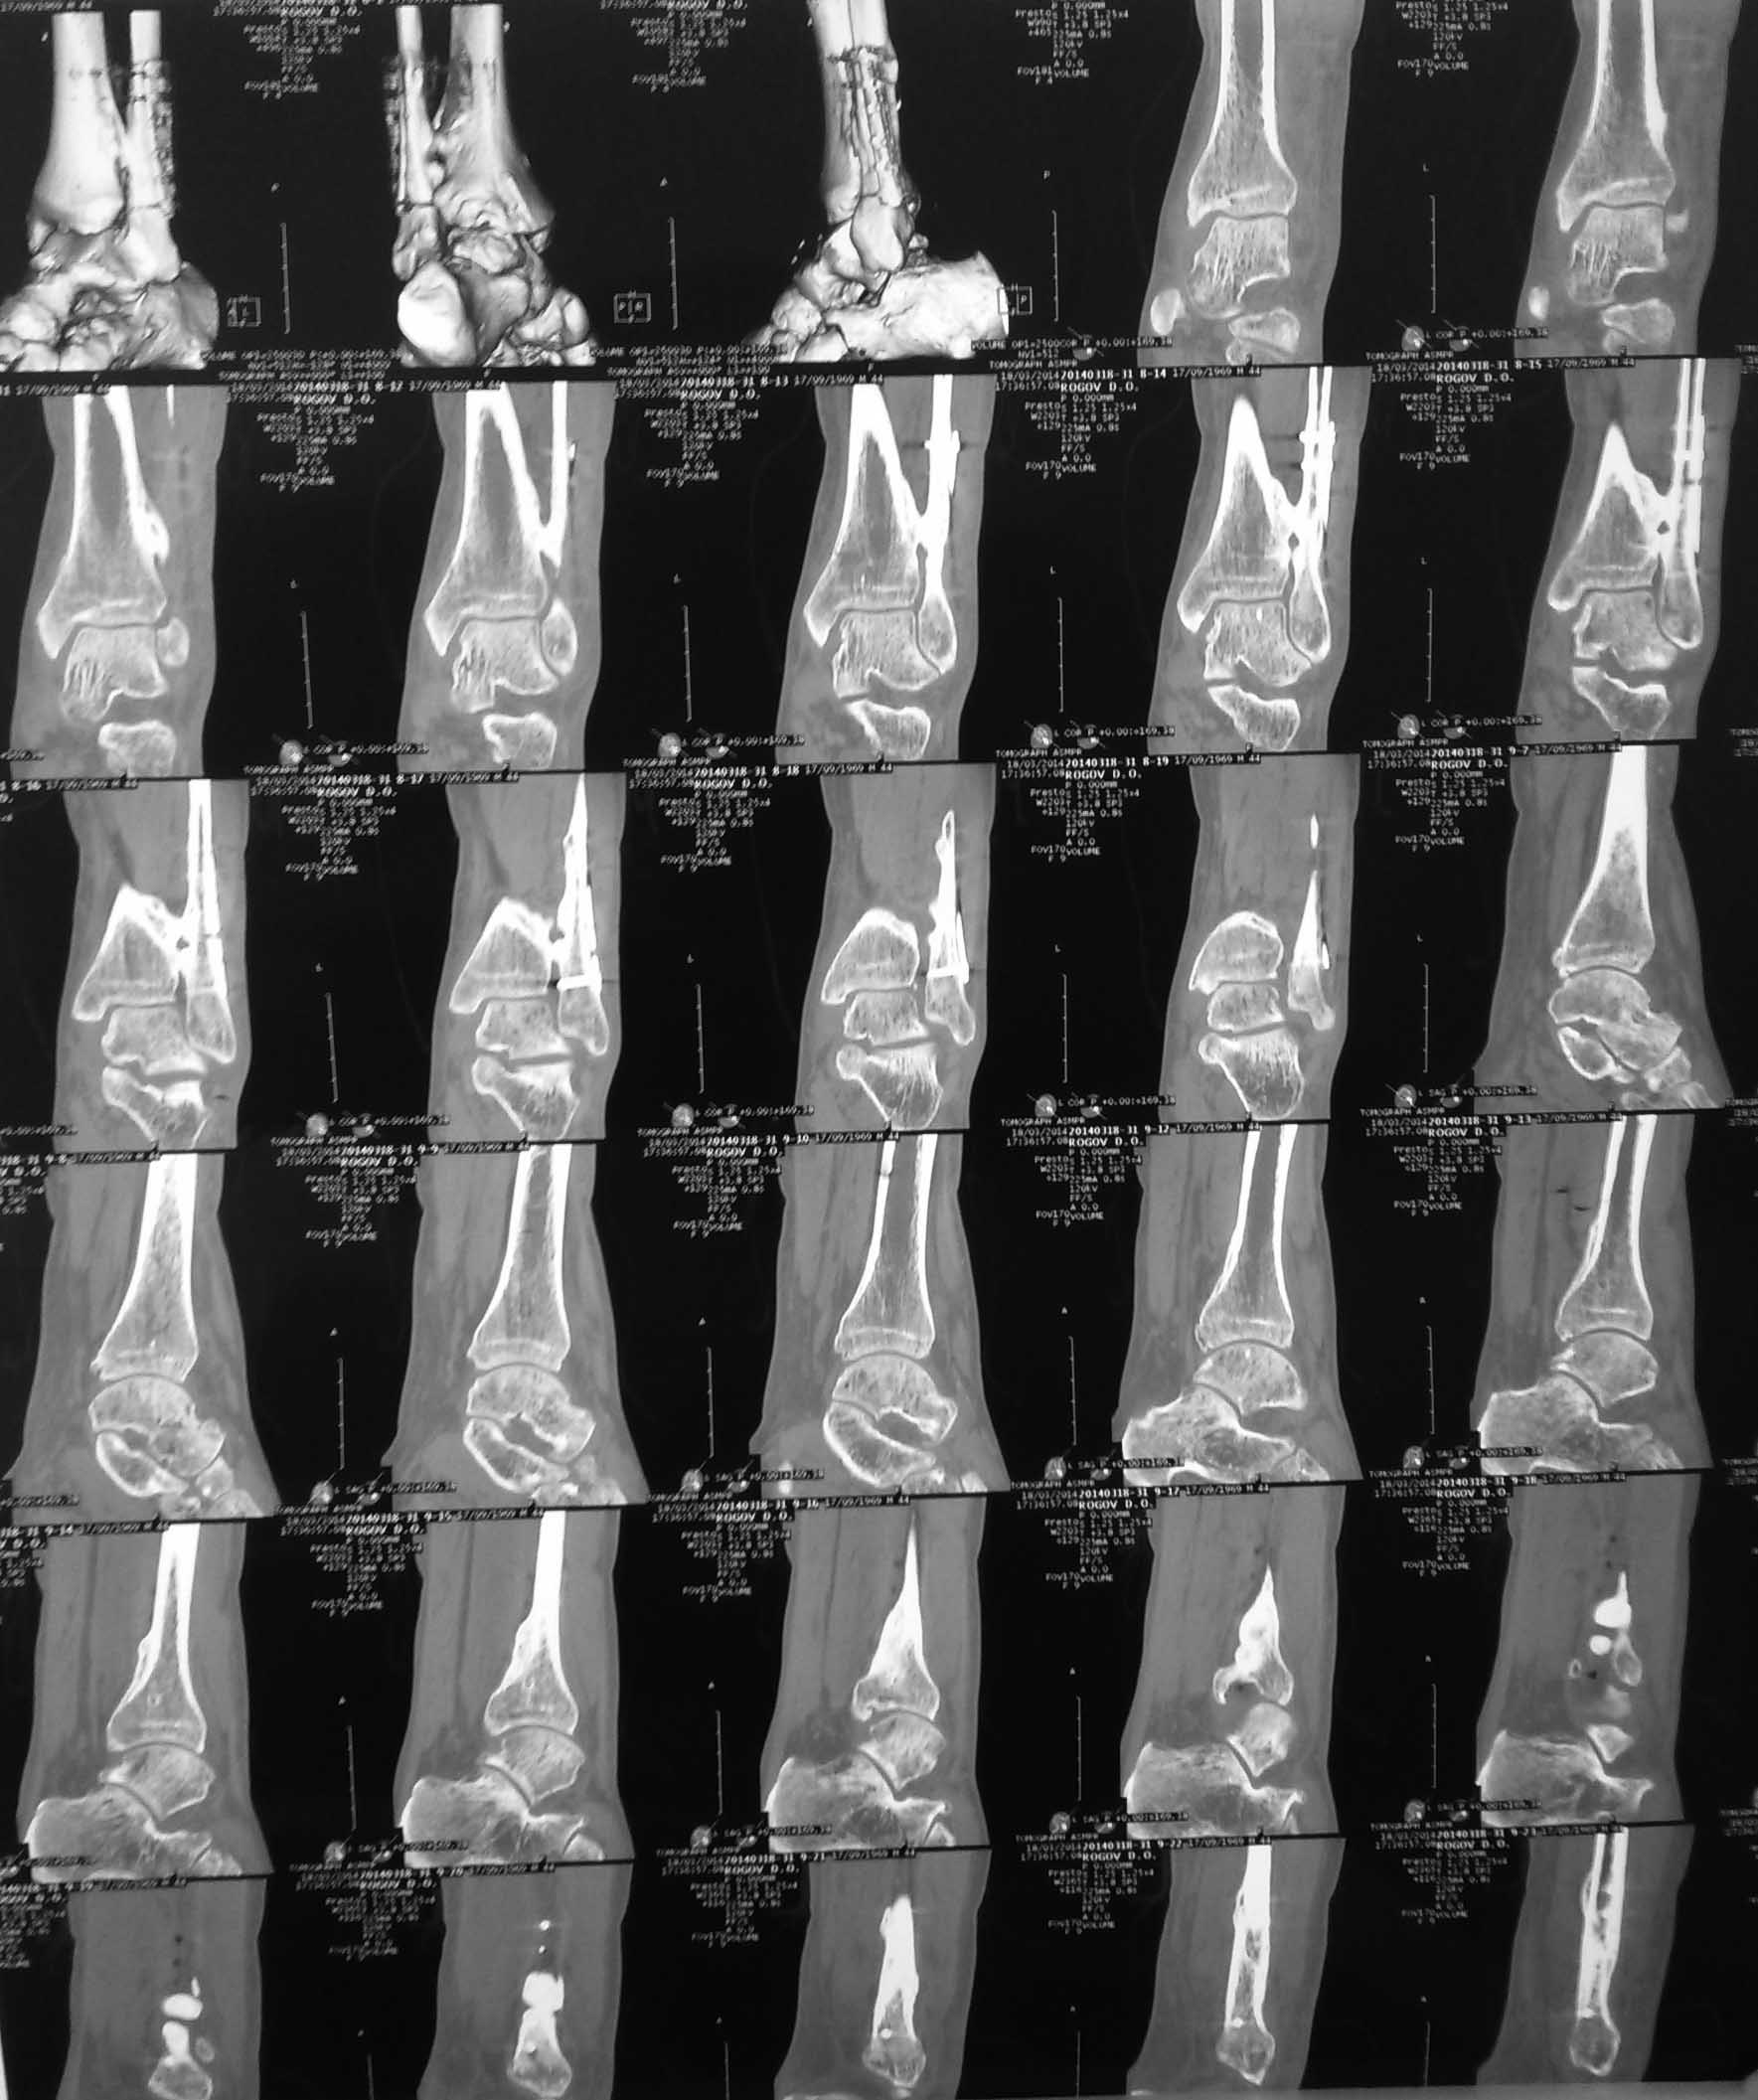

межберцовый синостоз

Пациент 43 года. Жалобы на боли в голеностопном суставе после нагрузок, умеренное ограничение движений в крайних положения, отёк стопы.

Травма в феврале 2013, подворот стопы, падение с высоты роста. Дз.: перелом малоберцовой кости н/3, повреждение дистального межберцового синдесмоза, дельтовидной связки, подвывих стопы наружу. Операция через 3 недели, без технических трудностей. Послеоперационный период по рекомедации АО, нагрузка, мобилизация, сроки. ЛФК под контролем лечащего врача и инструктора. Обращал внимание отёк больше обычного в после операционном периоде. Вопрос. Следует ли разделять синостоз, как избежать возможного рецидива, увидим ли мы отдалённый благоприятный эффект от этой операции? Избавим ли пациента от боли, увеличим ли движения в суставе?

Тут, на мой взгляд, проблема не в синостозе, а в ДОА. Наиболее вероятная причина - грубая хирургическая техника, но не факт.

Пусть ходит ... пока ходится, далее - протез или артродез на ваш вкус.